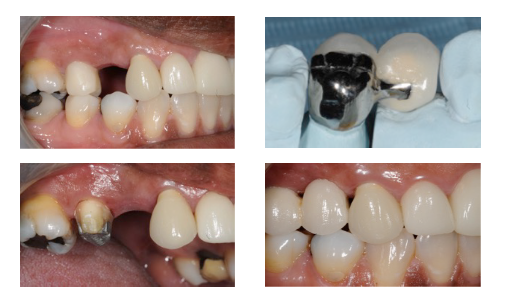

What are resin-retained cantilever bridges?

Bridges where the pontic is retained by a metal retainer using cement and abutment coverage.

cantilver= one side only attachment

reesin retained= retained by a metal retainer using cement and abutment coverage.

What is a key design feature of resin-retained bridges?

Minimal tooth preparation of abutment to maximize enamel bonding.

How should the abutment surface be prepared for resin-retained bridges?

Maximize coverage of the abutment tooth surface to maximise retention

What material and thickness should metal wing retainers have?

Rigid, non-precious metal with a thickness of 0.7(ant tooth`) -0.8mm (post tooth).